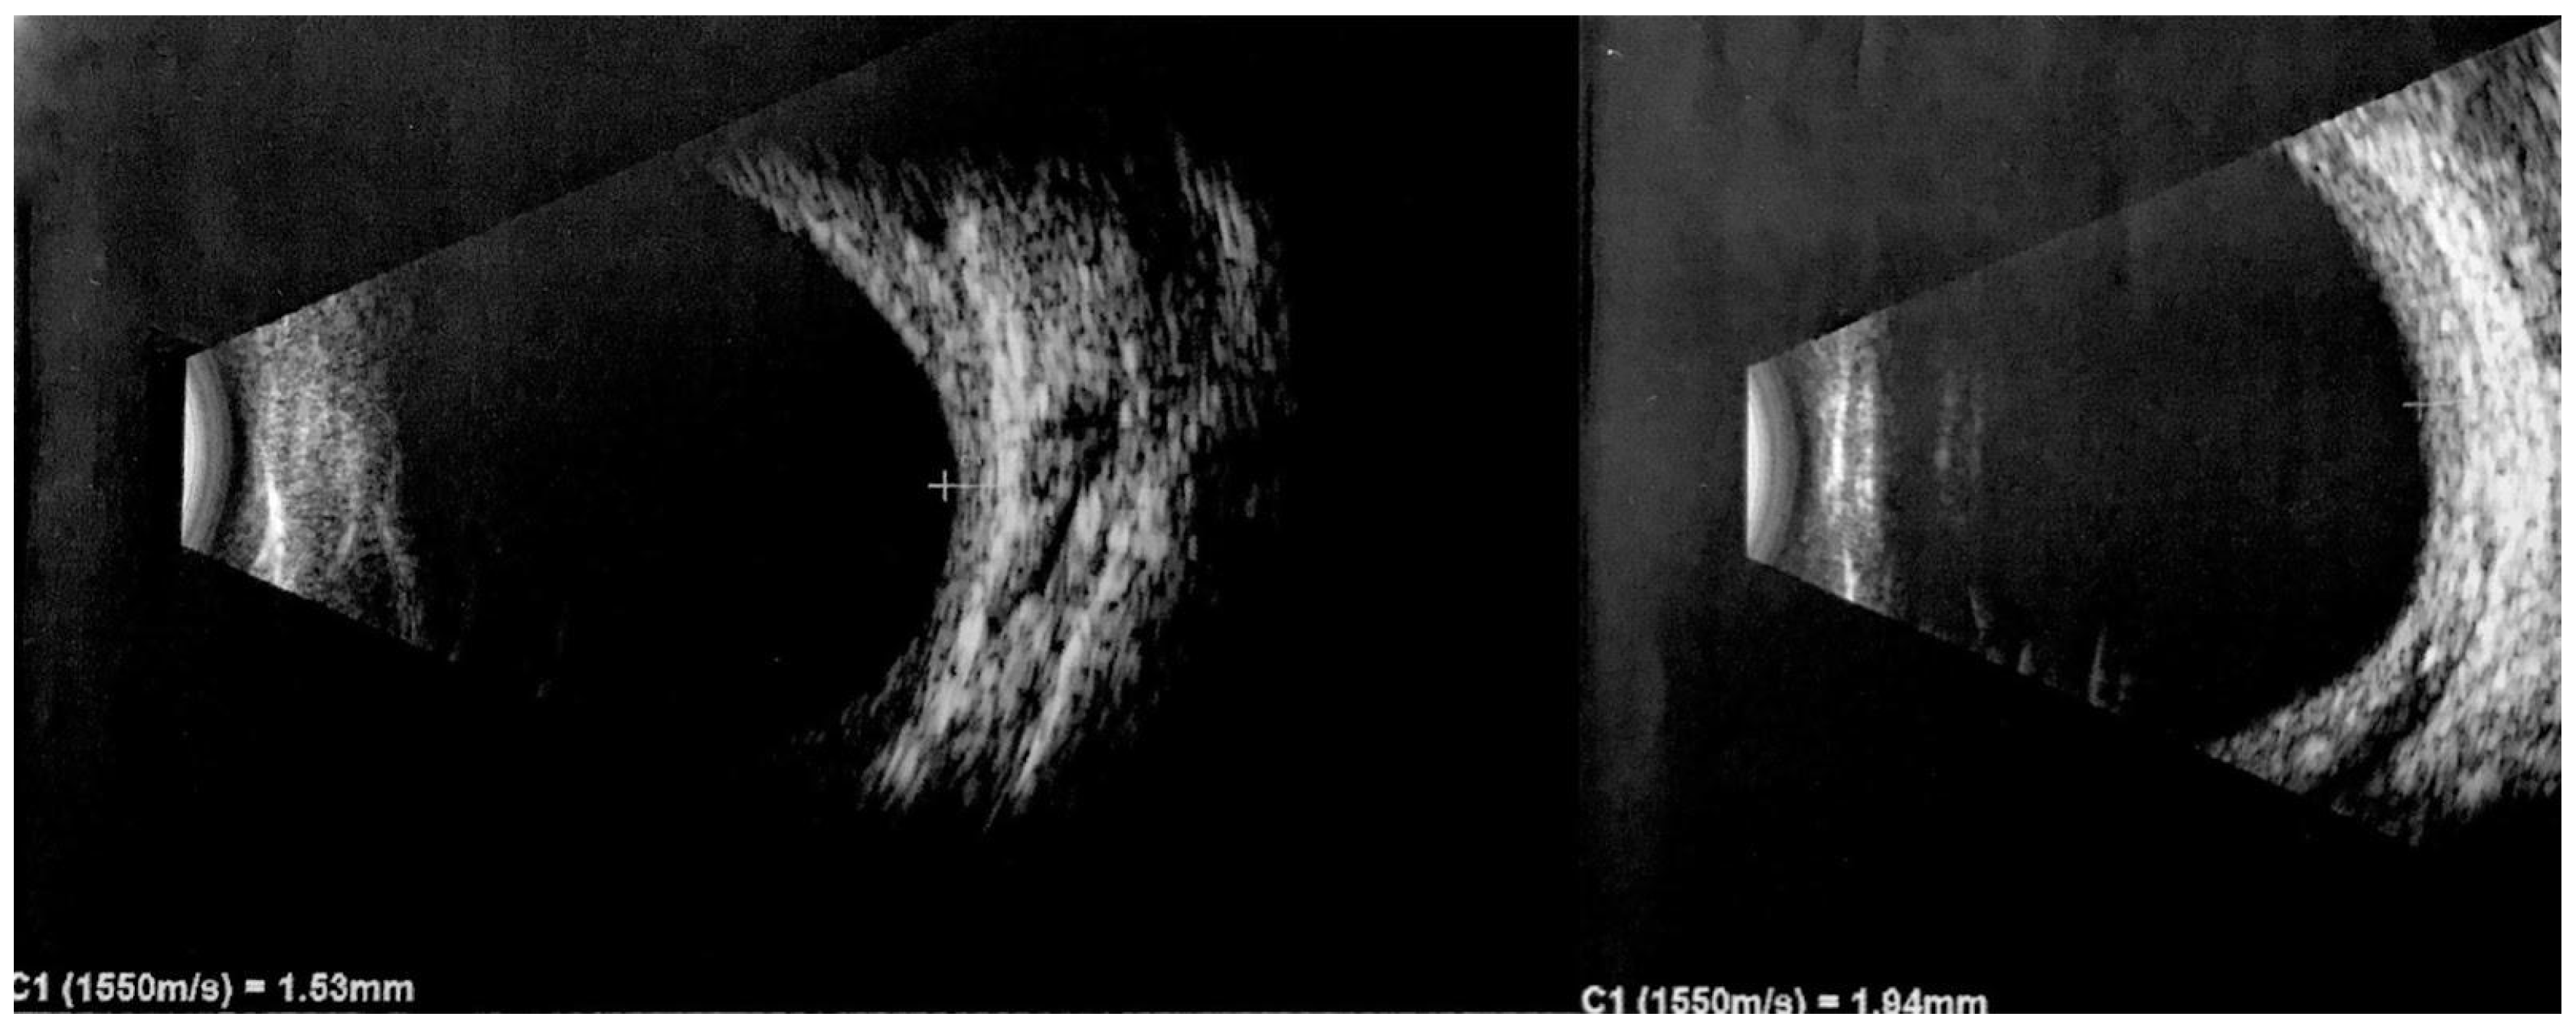

2.8. Ultrasound Imaging

| US Frequency: A-scan 7–10 MHz B-scan 10–20 MHz [75] | Cost effective, efficient. Helps in distinguishing DCH from malignant choroidal tumors such as melanomas. | It provides two-dimensional images and may not capture the full extent of complex hemangiomas or small lesions. | Benign tumors reveal a thickened choroid with pronounced internal reflectivity. DCH demonstrates a regular internal structure and lacks significant vascularization. DCH appears as a solid, dome-shaped lesion with hyperechogenicity and lacks a posterior shadow. Detects presence of associated features like retinal detachment and superficial calcifications. |